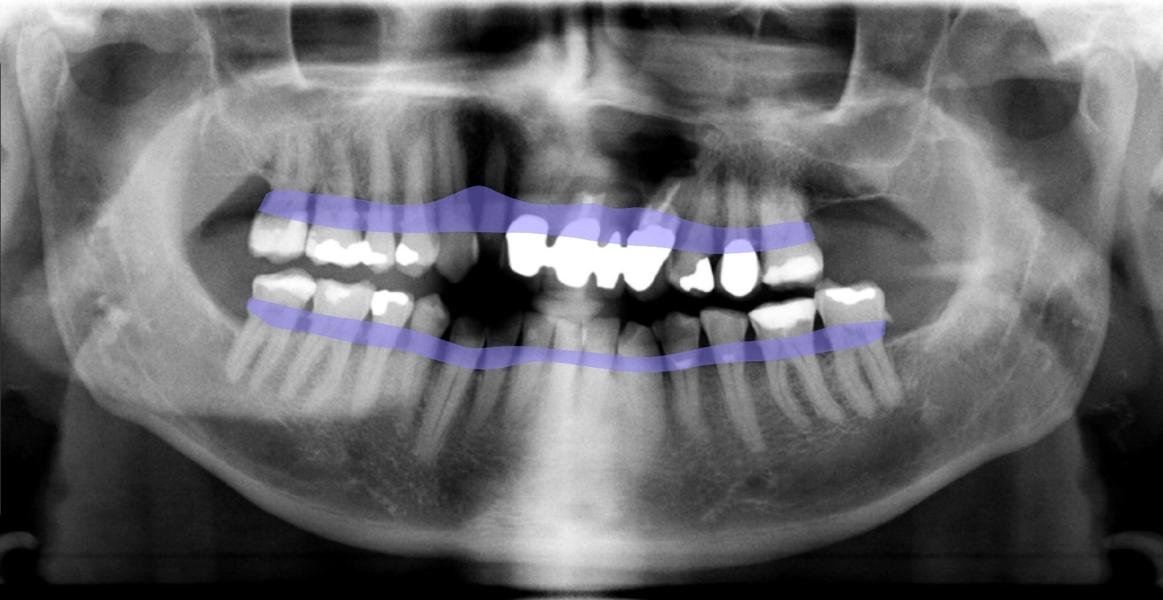

DENTAL XRAI

Zahnarztpraxis Kirste setzt auf künstliche Intelligenz

Technisch ist unsere Zahnarztpraxis stets am Puls der Zeit. Daher freuen wir uns, dass wir jetzt auch zu den Ersten gehören, die bei der zahnmedizinischen Diagnostik auf das KI-unterstützte Tool dentalXrai setzen. Die aus der Berliner Charité entwickelte Software ermöglicht uns eine sichere automatisierte Analyse zahnmedizinischer Röntgenbilder – und zwar in Sekundenschnelle. Die Bestätigung der ärztlichen Befundung durch die KI-Lösung schafft zudem mehr Sicherheit und Vertrauen.

„Mit dem neuen Tool sparen wir nicht nur wertvolle Arbeitszeit, sondern können unsere Patienten noch besser in die Diagnose einbeziehen. Die Röntgenbilder zeigen wir ihnen ab sofort einfach am iPad, das Tool dentalXrai markiert hier Infektionen und Karies farbig. So sind Röntgenbilder und die Diagnose für jedermann leicht zu verstehen“, erklärt ZA Klaus Kirste die Beweggründe, dentalXrai in der Praxis einzuführen.

Die Röntgenbilder können im Anschluss dann einfach als PDF an unsere Patienten versendet werden.